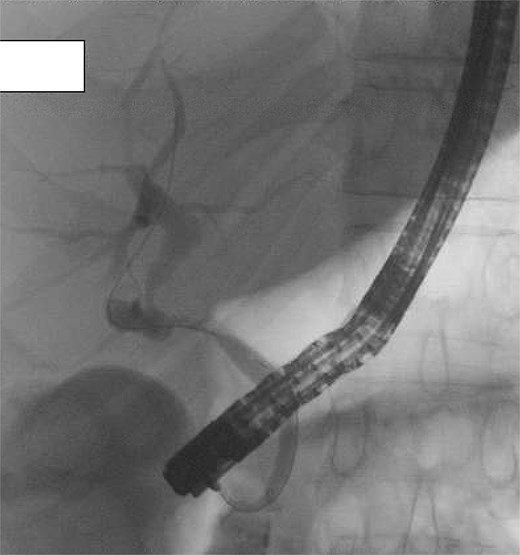

(A) Cholecystohepatic duct draining into infundibulum of gallbladder and then via cystic duct to ampulla of Vater. (B) Biliary anatomy following reconstituting subtotal cholecystectomy preserving infundibulum (arrow). (C) Anatomy of bile ducts and drainage following hepaticojejunostomy reconstruction.

On post-operative day 5, the patient developed abdominal pain and CT cholangiogram suggested possible bile leak. Endoscopic retrograde cholangiopancreatography (ERCP) demonstrated the flow of contrast into an elongated infundibular-cystic duct channel with no obvious bile leak, filling defects or CBD stricturing (Fig. 3). A sphincterotomy was performed and a 7Fr pigtail stent placed. Symptoms worsened and repeat CT cholangiogram demonstrated large volume intra-abdominal free fluid. On return to theatre, a pinhole perforation in the gallbladder remnant was identified as the source of bile leak, necessitating hepaticojejunostomy. A re-look laparotomy was performed 2 days later, after output >1 L of frank bile in the drain, where a revision hepaticojejunostomy with more proximal duct excision was performed using the Hepp-Couinaud technique [5] to manage anastomotic breakdown (Fig. 2C). The patient recovered well and was discharged. They remained well at 1 month follow-up. Histopathology demonstrated cholecystitis and cholelithiasis with no evidence of malignancy.

Post-operative ERCP demonstrating no filling defects, large stones, or extrinsic compression. Contrast drains from the liver into common hepatic duct and then via an elongated infundibular–cystic duct channel to the duodenum, supporting the diagnosis of a cholecystohepatic duct.